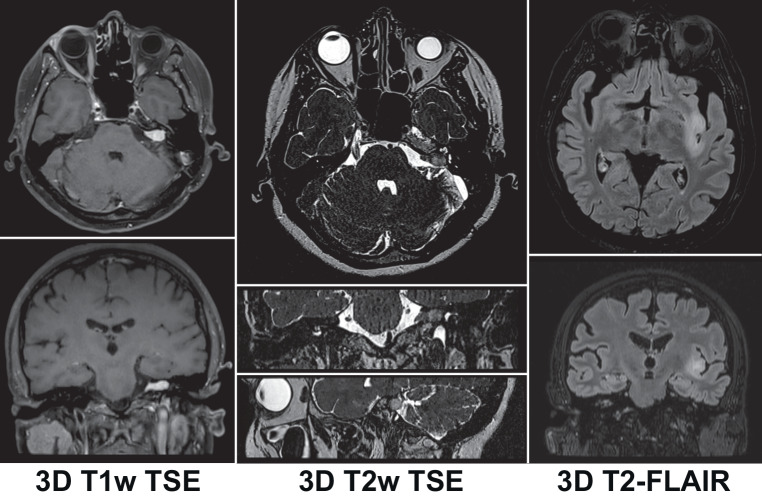

MRI protocols must be used that include 3D sequence protocols for all required image contrasts (e.g., 3D-T1w, 3D-T2w, 3D-T2-FLAIR) needed for target and organs-at-risk delineation (Fig. 4). (Consensus: 92%, abstention: 8%; Minimum requirement: 100%).

Fig. 4.

3D MRI sequences for intracranial SRT treatment planning. Left: 3D T1w TSE sequence in a patient with vestibular schwannoma. Center: 3D T2w TSE sequence in the same patient, Right: 3D T2-FLAIR sequence. Note: high-resolution multiplanar reconstruction